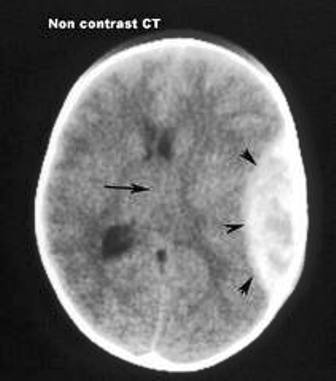

H́nh ảnh CT cho thấy khoảng máu tụ rất lớn ngoài màng cứng trên đầu trẻ

Sáng cùng ngày, cháu Đ. được mẹ chở đi học bằng xe gắn máy nhưng không đội mũ bảo hiểm. Gặp quăng đường trơn trượt, người mẹ bị ngă xe, cả hai mẹ con té văng ra đường, cháu bé dập nát vành tai trái và rách da đầu. Sau khi được bệnh viện địa phương sơ cứu, cháu được chuyển đến Bệnh viện Nhi Đồng 2, kết quả chẩn đoán h́nh ảnh cho thấy cháu đă bị chấn thương nặng ở vùng đầu.